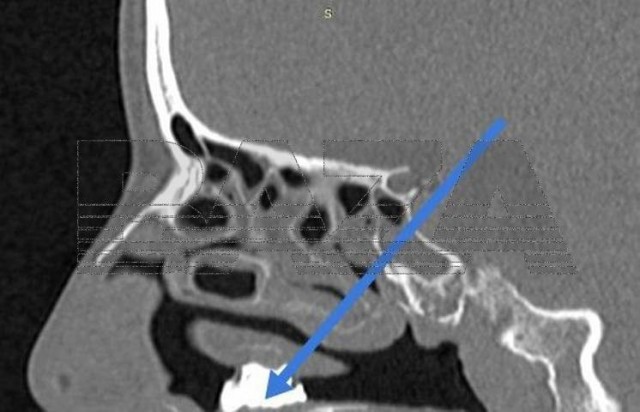

С его помощью она хотела вылечиться от насморка.

В Долгопрудненскую больницу обратилась 42-летняя женщина, которая целый год страдала от проблем с дыханием и обильных выделений из носа. Кроме того, в последний месяц добавился новый симптом — неприятный запах. Врачи осмотрели женщину и обнаружили у неё в носу кусок угля.

Медики тут же направили пациентку в стационар на операцию. За 40 минут врачи частями извлекли из носа женщины кусок угля, застрявший в грибковых наростах. Врачи подозревают, что уголь был всё-таки каменный — на это указывает твёрдость извлечённых частиц. Позже выяснилось, что таким образом женщина хотела вылечиться от мучившего её насморка. Почему она вдруг решила, что уголь в носу ей поможет - неизвестно.

После операции пациентка ещё несколько дней была под наблюдением медиков, а сейчас уже долечивается дома.

https://t.me/bazabazon/36070

Врачи добыли из носа женщины уголь